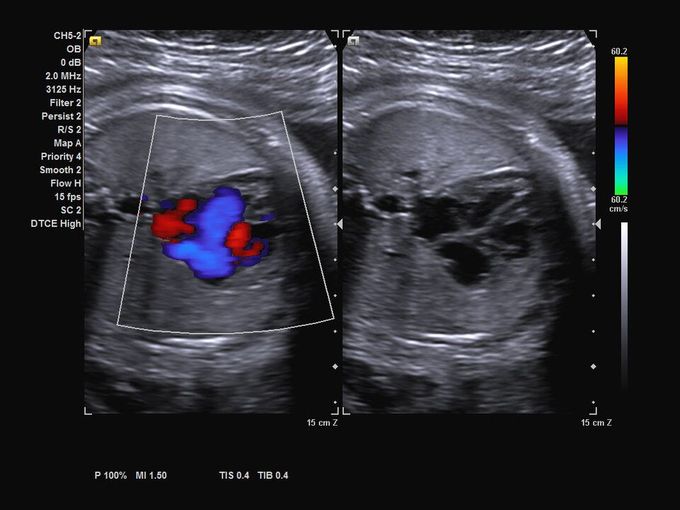

Кроме новой техники, можно заказать восстановленные медицинские системы: ультразвуковые сканеры, томографы, флюороскопы, ангиографы и хирургические установки С-дуга.